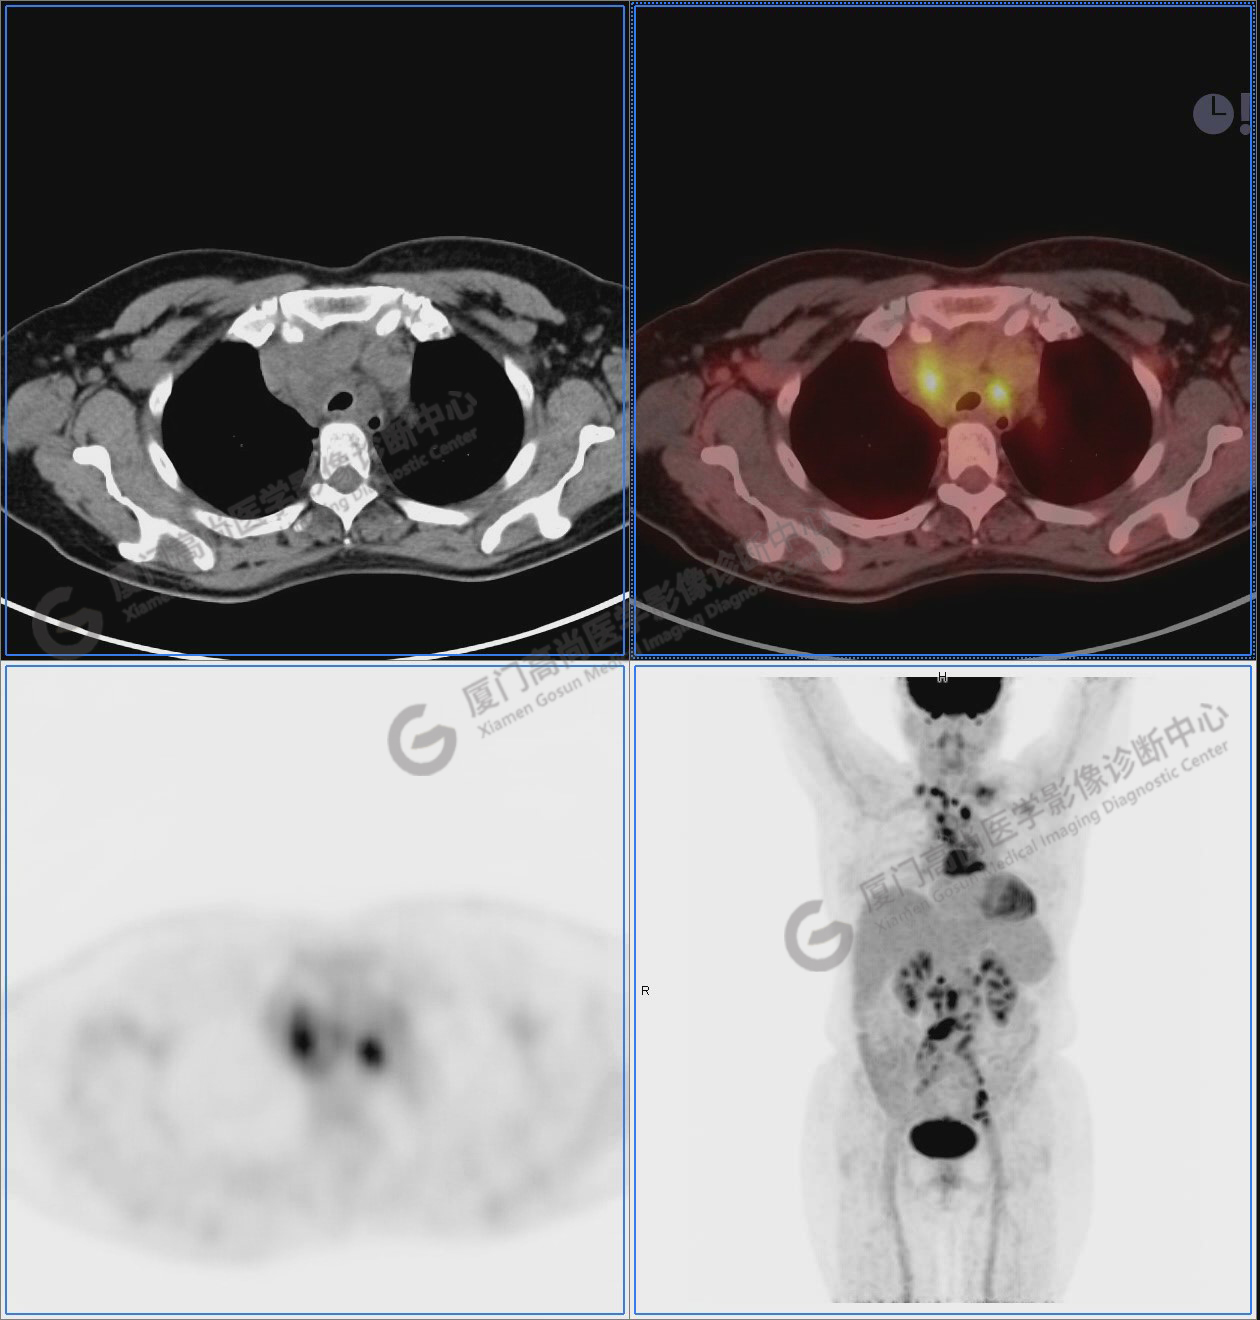

圖2-9:雙側(cè)鎖骨區(qū)、縱隔、右側(cè)內(nèi)乳區(qū)、腸系膜緣、腹膜后、雙側(cè)髂血管旁及盆腔多發(fā)腫大淋巴結(jié)影,代謝不同程度增高,考慮為轉(zhuǎn)移。

圖2

圖3

圖4

圖5